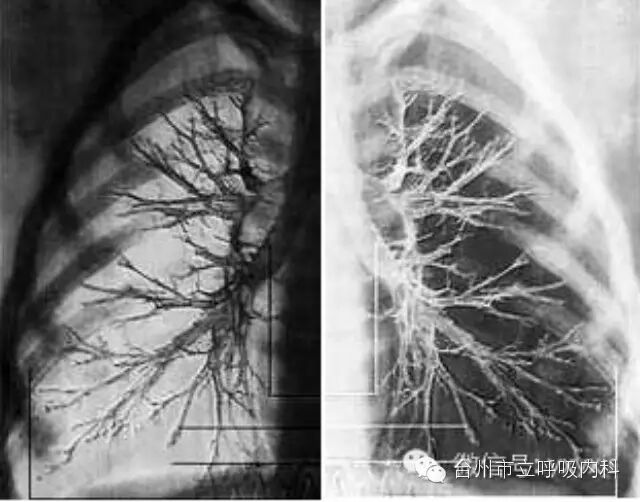

肺栓塞是急诊重症中最危急的情况之一,如何做到早期诊断为患者的抢救起到极为关键的作用,《CHEST》杂志这篇文章给出了一些答案。

肺栓塞每年死亡率高于乳腺癌, HIV / AIDS ,前列腺癌和机动车交通事故,这意味着其诊断相当重要以进行合适治疗。